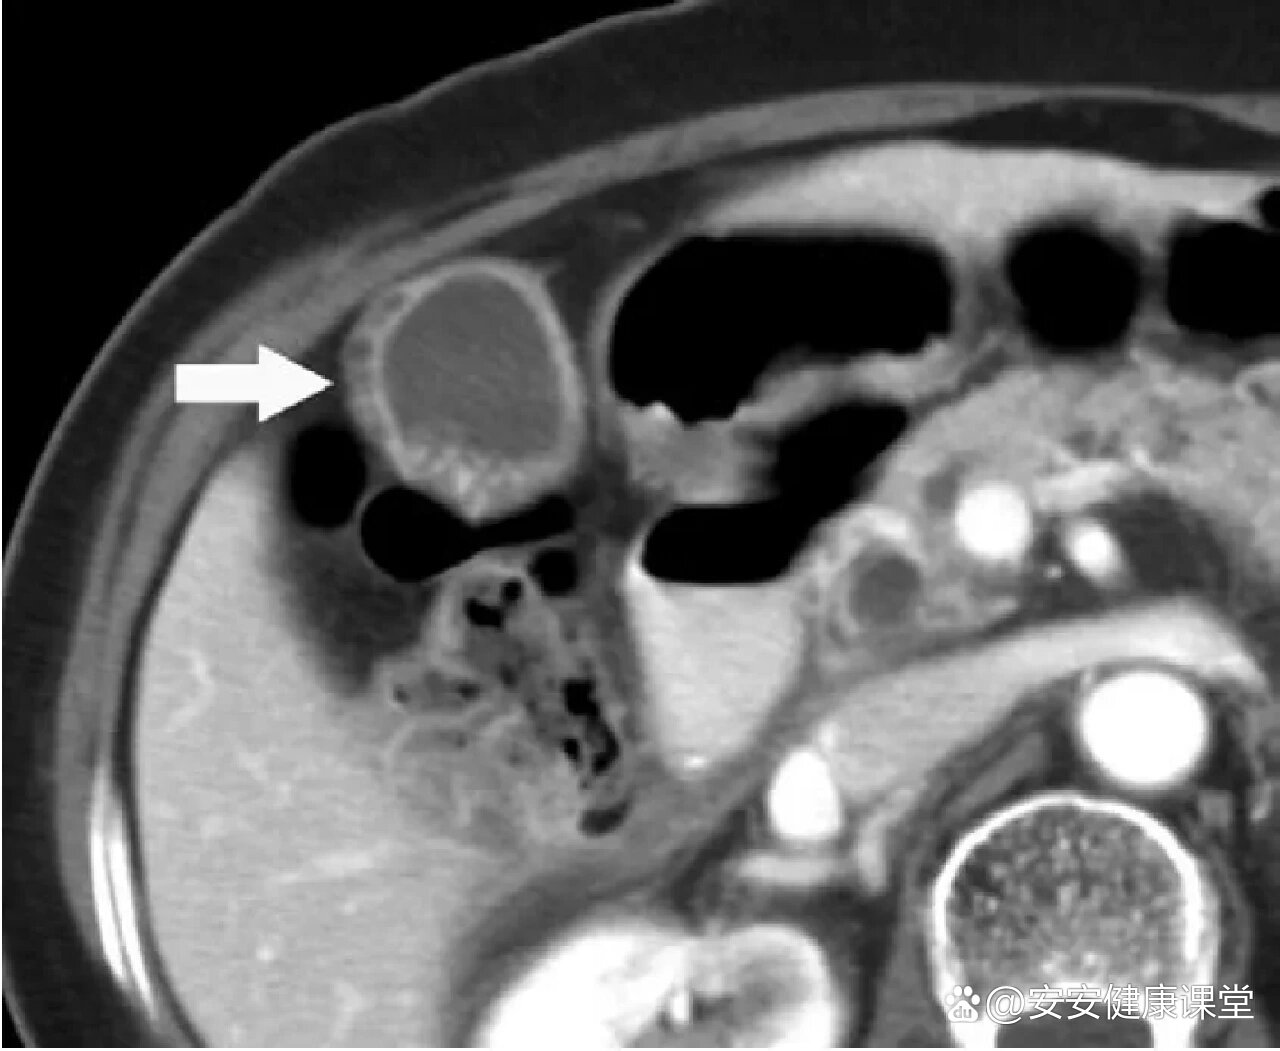

胆囊腺肌症ct图像

胆囊腺肌症影像表现及鉴别